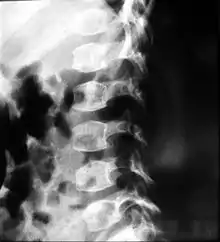

People with spondyloepiphyseal dysplasia are short-statured from birth, with a very short trunk and neck and shortened limbs. Their hands and feet, however, are usually average-sized. This type of dwarfism is characterized by a normal spinal column length relative to the femur bone. Adult height ranges from 0.9 meters (35 inches) to just over 1.4 meters (55 inches). Curvature of the spine (such as kyphoscoliosis and lordosis) progresses during childhood and can cause problems with breathing. Changes in the spinal bones (vertebrae) in the neck may also increase the risk of spinal cord damage. Other skeletal signs include flattened vertebrae (platyspondyly), a hip joint deformity in which the upper leg bones turn inward (coxa vara), and an inward- and downward-turning foot (called clubfoot). Decreased joint mobility and arthritis often develop early in life. Medical texts often state a mild and variable change to facial features, including cheekbones close to the nose appearing flattened, although this appears to be unfounded. Some infants are born with an opening in the roof of the mouth, which is called a cleft palate. Severe nearsightedness (high myopia) is sometimes present, as are other eye problems that can affect vision such as detached retinas. About one-quarter of people with this condition have mild to moderate hearing loss.[2]